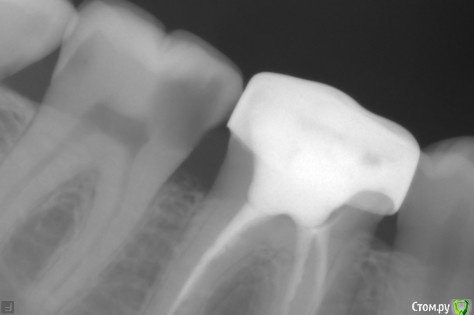

Иван_maa Опубликовано 30 октября, 2015 Поделиться Опубликовано 30 октября, 2015 В начале месяца зафиксировал кариес коренного зуба.Сегодня сходил на консультацию, сделал снимок, сказали, сто пульпит. Есть вероятность, что не будет, но очень малая. Есть клиники и врачи, которые могут вылечить без пульпита в Москве и Подмосковье ? За умеренную цену. фото прилагается. Ссылка на комментарий

Ker Опубликовано 27 ноября, 2015 Поделиться Опубликовано 27 ноября, 2015 Пульпит там, и еще полость средняя на дисталке. Ссылка на комментарий